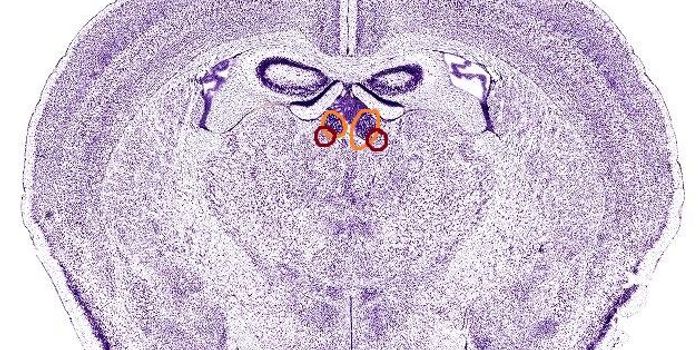

MAR 18, 2016Health & MedicineScientists have developed a brain implant that can turn the patient’s immune system against Alzheimer’s dise ...